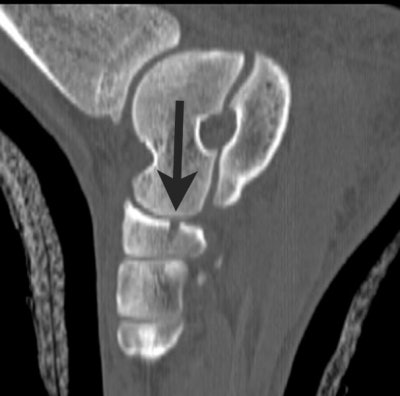

![]() |

| Sagittal reformatted image through the medial aspect of the foot demonstrates the fracture (arrow) of the inferior portion of the navicular. |